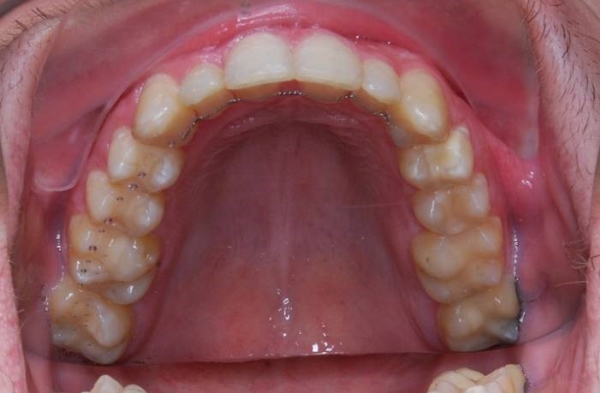

MUDr. Ondřej Suchý„Nejhezčích výsledků dosahujeme samoligovacími fixními rovnátky a snímatelnými foliovými rovnátky. I když i ostatními typy rovnátek, která používáme jde dosáhnout perfektního výsledku, léčba je u nich delší, složitější, méně pohodlná a některé extrémnější vady jsou s ostatními typy dokonce téměř neřešitelné. Proto, pokud to Vaše finanční situace umožňuje, volte snímatelná foliová rovnátka. Pokud si přejete levnější, fixní řešení, doporučuji samoligovací systém.“ |

Při běžné léčbě se snaží lékař dosáhnout zejména perfektního skusu. V této technice je kladen důraz na estetiku úsměvu a obličeje a to nejen v době léčby, ale bere se v potaz i stárnutí obličeje. Tzn., aby úsměv a obličej pacienta vypadal hezky nejen v době léčby, ale také 20 či 30 let po léčbě. Na to je při běžné technice rovnání často zapomínáno. Perfektní skus je samozřejmostí.

Během léčby se snažíme o dosažení širokého úsměvu. Nejen, že je nejhezčí, ale také nejlépe působí proti stárnutí obličeje.

Nejlépe je vidět tento efekt u starších pacientů, u kterých vede vyrovnání zubů touto metodou k výraznému omlazení vzhledu. Ideální počet viditelných zubů (horních) v úsměvu je deset. V Americe preferují dokonce dvanáct. Tomuto trendu jsou nejlépe uzpůsobená fixní rovnátka s použitím samoligovacích zámků a snímatelná foliová rovnátka.